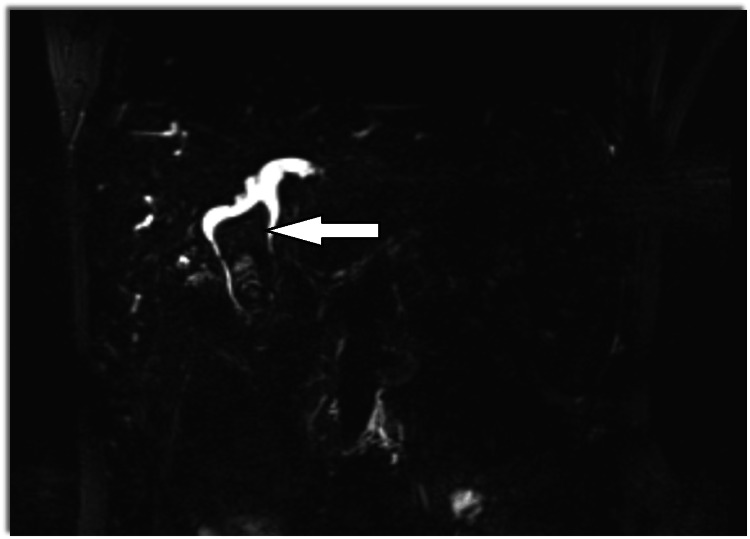

Magnetic resonance cholangiopancreatography (MRCP) showed dilatation of bi-lobar intrahepatic biliary radical (IHBR) with dilatated CBD large T2 hypointense and T1 (Figure 1), hyperintense calculus is seen, occupying dilated CBD and common hepatic duct (CHD). It extends into the left hepatic duct (LHD) and right hepatic duct (RHD), with the possibility of type 1c choledocholithiasis with cystolithiasis, and hepatolithiasis with cholelithiasis (Figures 2, 3).